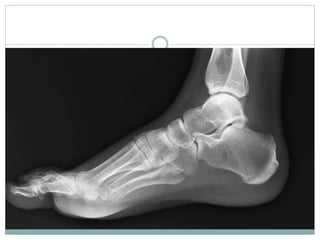

ANKLE & FOOT

BIOMECHANICS

BONES

 26 bones & 2 sesamoid bones; divided into 3 functional